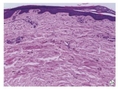

真皮黑素细胞增多症( dermal melanocytosis) 指 真皮中出现了含黑素的树突状黑素细胞,可分为先 天性和后天性两类。先天性真皮黑素细